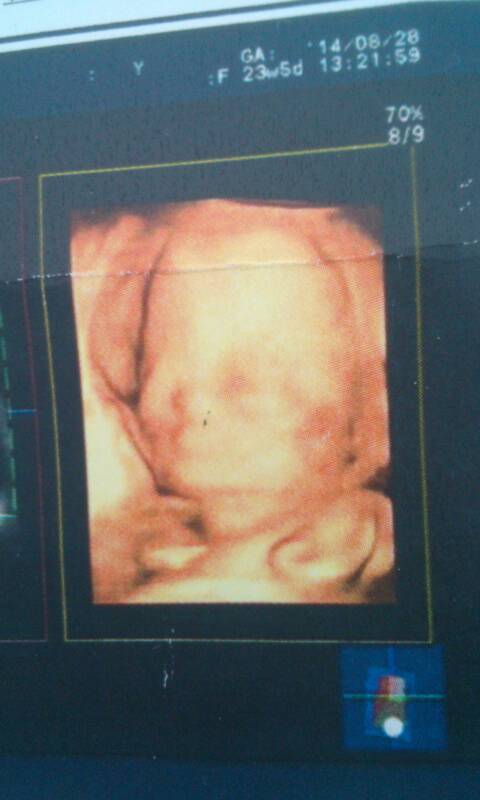

昨天照的四维,今天看宝宝脸上有块红红的,会不会是胎记啊 好怕,帮我看看 昨天照的四维,今天看宝宝脸上有块红红的,会不会是胎记啊。好怕,帮我看看 点击展开 153*****332_VxPQ 2014-08-29 11:03 为您推荐: 其他回答 B超照片中的红色跟我们平时看到的红色不是一回事的,医生没有说有血管瘤就不用自己瞎琢磨吓唬自己。 衷喜明2 2014-08-29 11:04 相关问题 宝宝屁股上红红的一块是不是就是胎记呀? 今天宝宝起了一身的小白疙瘩,周围红红的怎么回事 宝宝出生时后脑勺有红红的和胎记似得,现在还有,该怎么办?